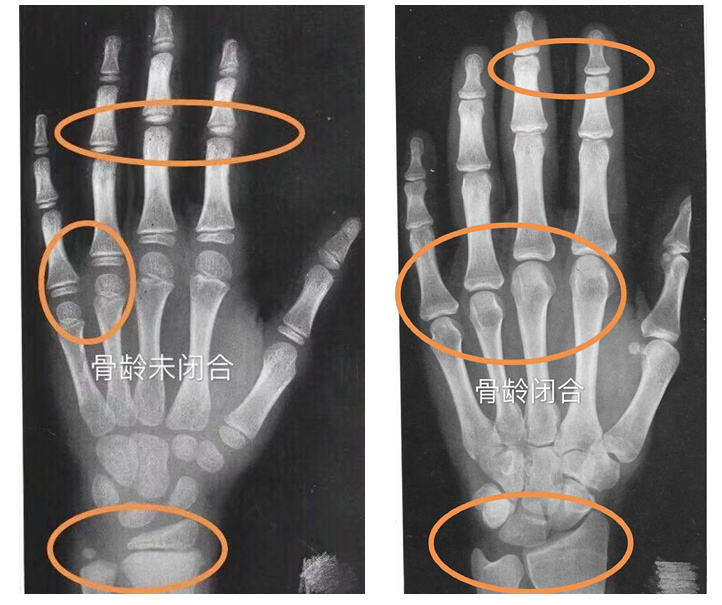

骨龄是衡量儿童和青少年生长发育的重要指标,它可以帮助我们了解孩子的生长发育是否正常,是否存在生长激素分泌不足、内分泌失调等问题。通过测量骨龄,可以及时发现并解决潜在的健康问题。